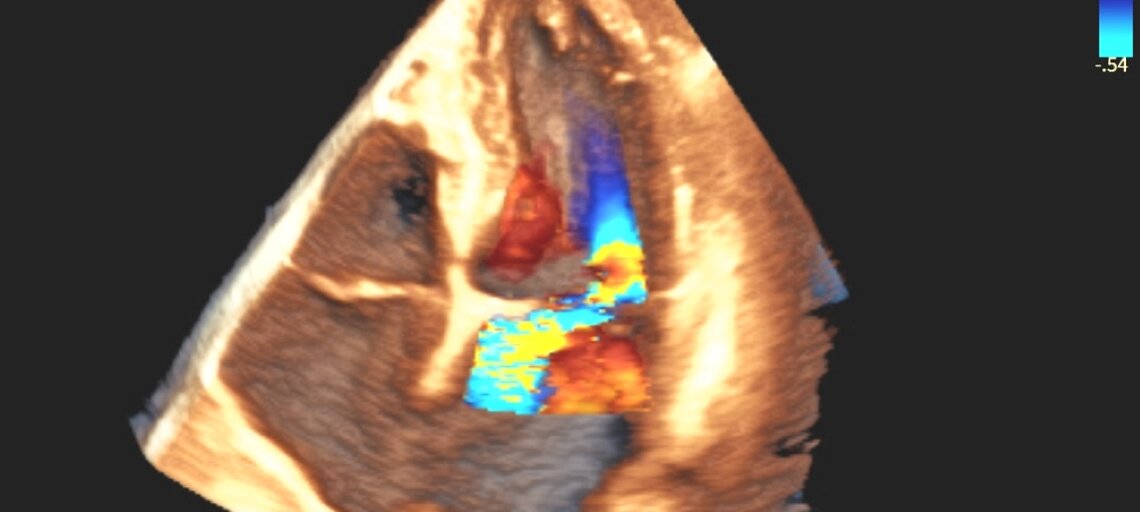

- Ecocardiogramma color-Doppler: è l’esame di riferimento per confermare la diagnosi, valutare la sede e l’entità del prolasso e la presenza di rigurgito.

- Ecocardiogramma transesofageo: utile quando servono immagini più dettagliate, ad esempio in vista di un eventuale intervento di riparazione.